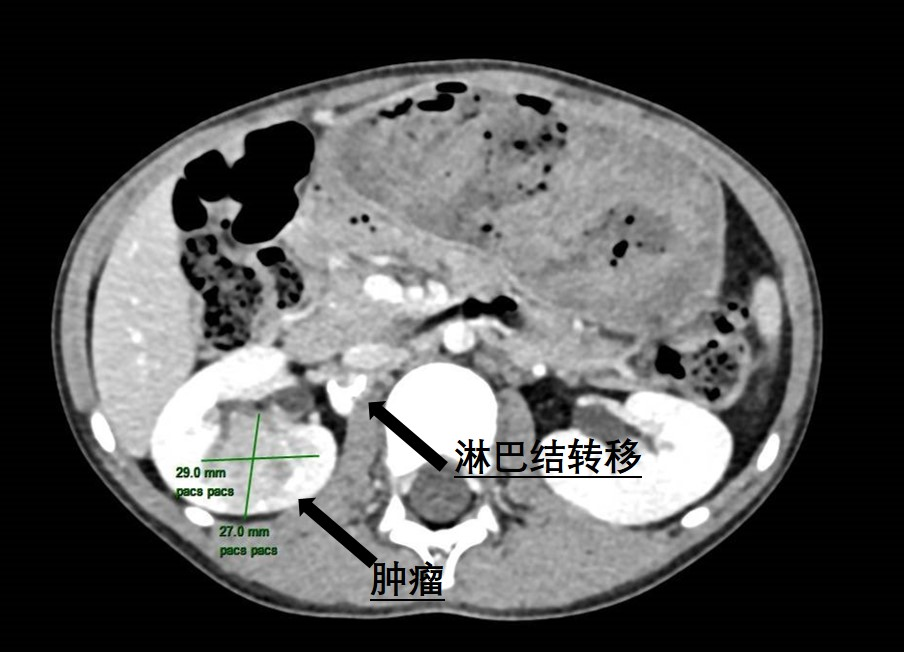

近日,老虎机app (简称老虎机app )泌尿外科为一名6岁患儿成功实施了腹腔镜下右侧肾肿瘤根治性切除伴转移淋巴结清扫手术,帮助患儿切除了罕见肾脏肿瘤。不久前,朵儿(化名)的妈妈无意中发现女儿反复血尿,这让全家人都陷入了焦虑与不安。为了尽快查找原因,朵儿妈妈带着女儿来到我院就诊。当天,她们刚好碰上我院的大型健康义诊活动,于是便找到了泌尿外科主任曾钦松教授问...